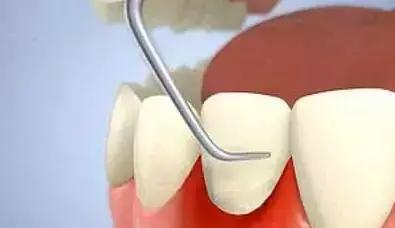

(2).龈下牙石:位于龈缘以下、龈袋或牙周袋内的根面上,肉眼不能直视,必须用探针探查,方能知其沉积部位和沉积量。龈下牙石中无机盐的主要来源是龈沟液。 牙石对牙周策划的危害,主要是构成了菌斑附着和细菌滋生的良好环境。

1.牙周袋形成:由于炎症的扩展,牙周膜被破坏,牙槽骨逐渐吸收,牙龈与牙根分离,使龈沟加深而形成牙周袋。可用探针测牙周袋深度。